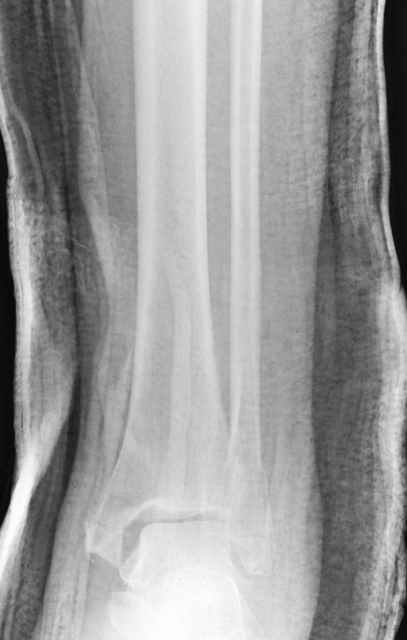

-С появлением новых имплантов, которые делятся на правые и левые, задней или латеральной аппликации, жесткие с локинг концепт, которые сидят на кости анатомически, применение 1/3 тубулярных пластинок

отходит на второй план из-за ее слабости. Если применить 2 пластины уложенные друг на друга, слабость этих пластинок можно скомпенсировать.

Слабая несостоятельная пластина приводит к вальгусной деформации и риск осложнений нарастает, особенно если линия перелома находится выше

метафизарной зоны, в диафизе, где имеется риск замедленного сращения, тогда адекватно применение более жесткой конструкции 3.5 мм динамической компрессионной пластины.

При косых переломах малоберцовой кости применение пластин отличается от обычных, показание antiglade technique-методика против скольжения, потому что укорочение длины малоберцовой кости чреваты ранними артрозами.

Из работ Ramsey and Hamilton, Yablon et., укорочения на 1мм

малоберцовой кости, уменьшает на 42% контактную поверхность между

малоберцевой и таранной кости, которое в свою очередь приводит к

увеличению давления на остальные части суставной поверхности, что

является предпосылкой раннего артроза.